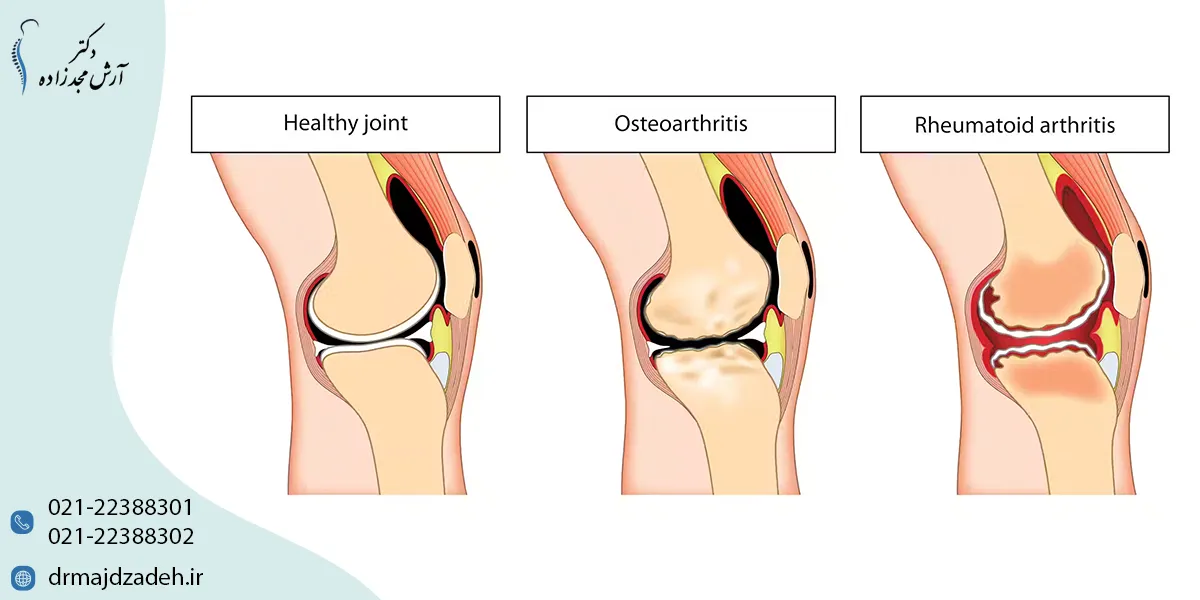

آرتروز زانو چیست؟

آرتروز زانو یا Knee Osteoarthritis یک بیماری دژنراتیو مفصلی است؛ به این معنا که بهمرور زمان غضروف مفصل زانو تخریب شده و توانایی آن در جذب فشار کاهش مییابد. در حالت طبیعی، غضروف مانند بالشتکی نرم بین استخوانهای ران و ساق قرار دارد و مانع سایش آنها میشود. با شروع آرتروز مفصل زانو، این غضروف نازک شده و در نهایت از بین میرود، بهگونهای که استخوانها روی هم ساییده میشوند. همین موضوع علت اصلی درد، تورم و محدودیت حرکتی در بیماران مبتلا است.

علائم آرتروز زانو چیست؟

نشانههای آرتروز مفاصل زانو بهصورت تدریجی ظاهر میشوند و شدت آنها با گذر زمان افزایش مییابد. در مراحل اولیه ممکن است بیمار تنها کمی خشکی یا درد خفیف داشته باشد، اما در صورت پیشرفت بیماری، حرکتهای ساده مانند بالا رفتن از پله یا حتی راه رفتن معمولی هم دشوار میشود. مهمترین علائم عبارتاند از:

تورم و التهاب

به دلیل تخریب غضروف و التهاب بافت اطراف مفصل، تورم در ناحیه زانو شایع است. این تورم ممکن است همراه با احساس گرمی در مفصل باشد. التهاب باعث بدتر شدن درد و محدود شدن حرکت میشود.

تشخیص آرتروز زانو

تشخیص بهموقع آرتروز مفاصل زانو اهمیت زیادی دارد، زیرا شروع درمان در مراحل اولیه میتواند روند بیماری را کندتر کند و کیفیت زندگی بیمار را بهبود دهد. روشهای اصلی تشخیص شامل:

تصویربرداری (X-ray, MRI)

- X-ray (رادیوگرافی): تغییرات استخوانی مانند باریک شدن فضای مفصلی یا وجود زوائد استخوانی (استئوفیت) را نشان میدهد.

- MRI: جزئیات بیشتری از بافت نرم شامل غضروف، مینیسکها و رباطها ارائه میدهد و برای تشخیص زودهنگام آرتروز مفصل زانو بسیار مفید است.